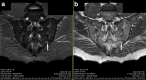

Current emphasis on diagnosing axial spondyloarthritis (axSpA) in early stage enforced the search for sensitive and specific diagnostic algorithms with the use of imaging methods. The aim of this review was to summarise current recommendations concerning the use of imaging techniques in diagnostics and monitoring of axSpA as well as to outline possible future directions of the development in this field. MEDLINE database was searched between March and April 2018. In the first phase, such keywords were applied: 'ASAS', 'EULAR', 'ASAS-EULAR', 'ASAS/OMERACT', 'axial spondyloarthritis', while in the second step: 'axial spondyloarthritis', 'ankylosing spondylitis', 'magnetic resonance imaging', 'computed tomography', and 'radiography', 'imaging'. An up-to-date summary of European League Against Rheumatism (EULAR) recommendations enriched with recent updates of Assessment of Spondyloarthritis International Society (ASAS) diagnostic criteria regarding imaging in axSpA course was created. Moreover, we outlined the role of new in this field, promising imaging techniques, such as diffusion-weighted imaging and dynamic contrast-enhanced sequences in magnetic resonance imaging (MRI) or low-dose computed tomography (CT). As precise monitoring of axSpA activity is vital, we reviewed the most precise methods: semiquantitative scores (e.g., Spondyloarthritis Research Consortium of Canada scores or CT Syndesmophyte Score) and quantitative analysis of MRI-based apparent diffusion coefficient or perfusion maps and enhancement curves. According to EULAR and ASAS recommendations, radiography and MRI still remain basic methods of axSpA diagnostics and monitoring. However, the knowledge of state-of-the-art international guidelines combined with the awareness of emerging imaging methods is the key to effective management of axSpA.